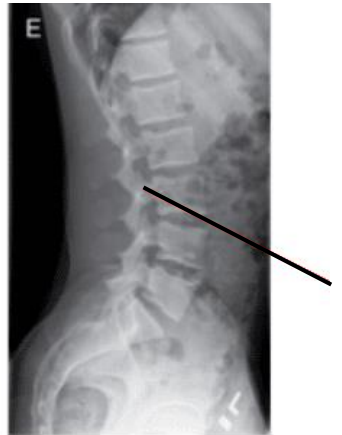

A imagem radiográfica abaixo demonstra qual detalhe anatômico:

https://www.cintramedica.pt/exame/raio-x-coluna-lombar